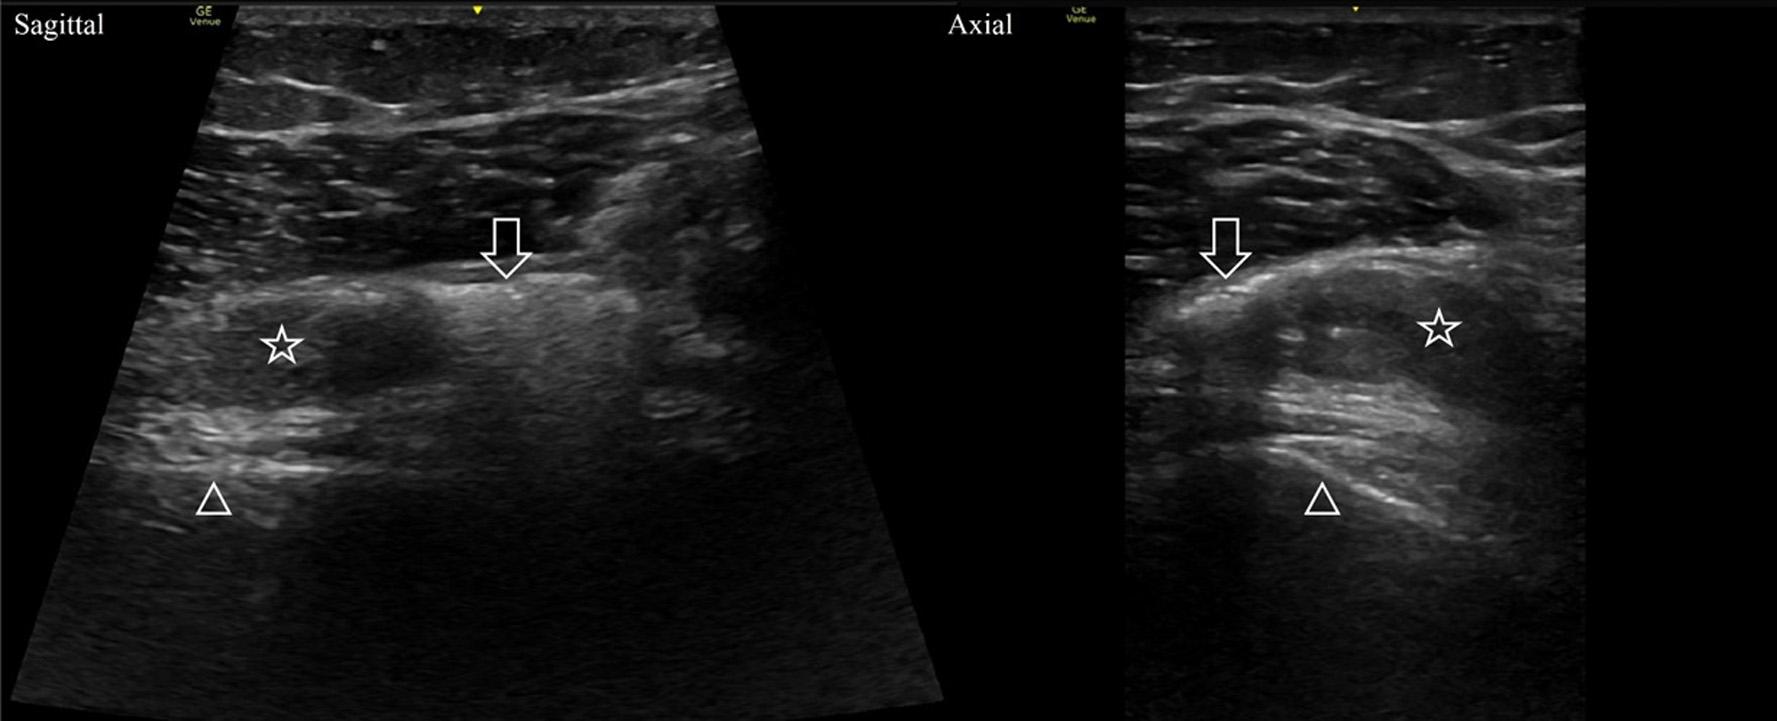

A20-year-oldmalepresentedtotheEDwithagunshot woundtotheanterior,rightknee.Hereporteddifficulty walkingandlimitedrangeofmotionoftheknee.Onphysical examination,hehadtwomissilewoundsonthemedialaspect ofhisleg:onesuperiortothepatellaandoneinferiortothe tibialplateau.Theinitialradiographshowednooccult fracturebutdemonstratedbulletfragmentsneartheknee joint.APOCUSexaminationbytheemergencyphysician (EP)scanningthesuprapatellarrecessshowedinternal hyperechoiclinearstructuresconcerningforfreeair (Image2,Case1)withinhypoechoiceffusionwithanechoic bubblesconcerningforlipohemarthrosis.TheEPmadethe preliminarydiagnosisofTAK.ACTwasorderedtoconfirm TAK,butduetotheovernightburdenoftraumapatientsit wasnotperformeduntilsevenhoursafterpresentationwith interpretationtakinganadditionalhour.Orthopedicstook thepatienttotheoperatingroom(OR)thefollowingdayfor irrigationanddebridementwhereTAKwasconfirmed.The patientwasgivenaprophylacticseven-daycourseof cephalexin500milligrams(mg)everysixhoursand aone-weekfollow-upwithorthopedics.

A20-year-oldmalepresentedtotheEDwithadeep lacerationtotheleftkneeafterabicycleaccident fivehours prior.Onexamination,therewasadeep,15-centimeter(cm) longinfrapatellarlacerationwithexposedbutintacttendon. Thepatientwasambulatory,withoutneurologicdeficits,and hadfullrangeofmotionoftheleftknee.APOCUS examinationoftheleftkneewasperformedbytheEPand showedahypoechoicjointeffusioninthesuprapatellarspace

thatcontainednumerousmobile,hyperechoicstructures withposteriorshadowingalongthesuperioraspectofthe fluidcollection,suggestiveofTAK(Image2,Case2). Subsequentradiographsofthekneedemonstratednobony injurybutapossiblesmallfocusofgasinthesuprapatellar recess.Computedtomographyconfirmedthepresenceofgas withinthekneejointwiththeadditional findingofasmall, leftfemoralcondyleavulsionfracture.Thewoundwas irrigatedwithnormalsalineanddressed.Orthopedicswas consulted,andthepatientwasstartedonvancomycin intravenously.HewastakentotheORthenextdayfor irrigationandprimaryrepairofthejointcapsule.

APOCUSexaminationofthekneejointwasperformed bytheEPshowingahypoechoicjointeffusioninthe suprapatellarrecesswithhyperechoicstructureswith posteriorshadowing(Image3).These findingswere interpretedasahemarthrosiswithintra-articularairbubbles suspiciousforTAK.Orthopedicswasconsulted,which confirmedthearthrotomywithapositiveSLT.Thepatient wastreatedwithonegramofcefazolinandtetanus vaccinationupdate.Orthopedicsperformedsalineirrigation ofthejointandprimaryrepairofthecapsulelacerationatthe bedside.Thepatientwasdischargedonaprophylacticcourse ofcephalexin500mgeverysixhoursfor fivedays.At two-weekfollow-upwithorthopedicsshehadnosignsof jointinfection.

Image2. Case1)Asagittalviewofthesuprapatellarrecessshowingahyperechoicfocusofairwithposteriorshadowing(arrow)withinan effusion(star).Theeffusionhasmultiplecomponents,whichisindicativeoflipohemarthrosis.Case2)Asagittalviewofthesuprapatellar recessshowingahyperechoicfocusofairwithposteriorshadowingandreverberationartifact(arrow).Notehowthesignalfromthecortexof thefemur(triangle)isobscuredbytheshadowing.Asmalljointeffusionisalsovisualized(star).

Image3. Sagittalandaxialviewsofthedistalfemurshowinghyperechoicfociwithposterioracousticshadowing(arrows)withinahypoechoic hemarthrosis(stars).Notetheshadowingobscuresthesignalfromthefemurcortex(triangles).